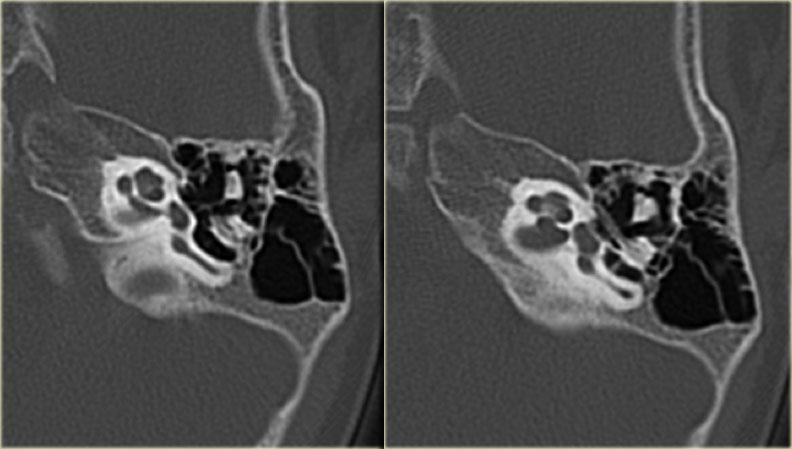

Bên trái là hình ảnh của một bé trai 2 tuổi với teo ống tai ngoài xương hai bên.

Xương búa và xương đe hợp nhất (mũi tên).

Ốc tai bình thường.